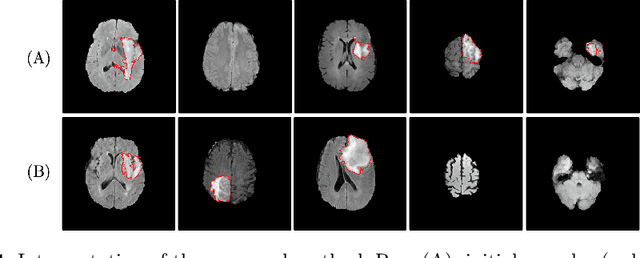

Abstract:Machine learning has been widely adopted for medical image analysis in recent years given its promising performance in image segmentation and classification tasks. The success of machine learning, in particular supervised learning, depends on the availability of manually annotated datasets. For medical imaging applications, such annotated datasets are not easy to acquire, it takes a substantial amount of time and resource to curate an annotated medical image set. In this paper, we propose an efficient annotation framework for brain MR images that can suggest informative sample images for human experts to annotate. We evaluate the framework on two different brain image analysis tasks, namely brain tumour segmentation and whole brain segmentation. Experiments show that for brain tumour segmentation task on the BraTS 2019 dataset, training a segmentation model with only 7% suggestively annotated image samples can achieve a performance comparable to that of training on the full dataset. For whole brain segmentation on the MALC dataset, training with 42% suggestively annotated image samples can achieve a comparable performance to training on the full dataset. The proposed framework demonstrates a promising way to save manual annotation cost and improve data efficiency in medical imaging applications.

Abstract:Machine learning has been widely adopted for medical image analysis in recent years given its promising performance in image segmentation and classification tasks. As a data-driven science, the success of machine learning, in particular supervised learning, largely depends on the availability of manually annotated datasets. For medical imaging applications, such annotated datasets are not easy to acquire. It takes a substantial amount of time and resource to curate an annotated medical image set. In this paper, we propose an efficient annotation framework for brain tumour images that is able to suggest informative sample images for human experts to annotate. Our experiments show that training a segmentation model with only 19% suggestively annotated patient scans from BraTS 2019 dataset can achieve a comparable performance to training a model on the full dataset for whole tumour segmentation task. It demonstrates a promising way to save manual annotation cost and improve data efficiency in medical imaging applications.